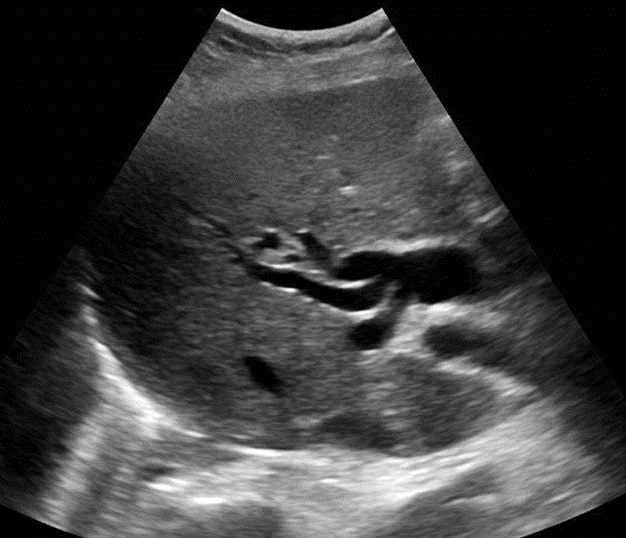

Aspect hyperechoriche

avec de zone de faible acoustique posterieure d'une calcul du

canal hepatique ( fleche blanche ) . Voie

biliaire en amont est tres dilate . Image

echographique per cutanee en coupe a longitudinal de

voie biliare principale |